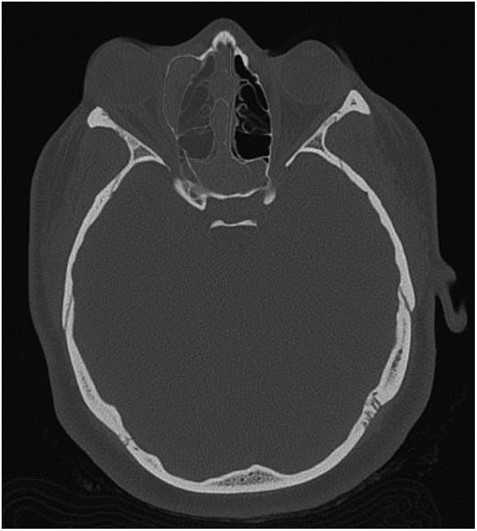

The results of the CT indicated complete opacification of the frontal, ethmoidal, sphenoidal and maxillary sinus on the right side with hyper-dense intraluminal soft tissue filling the sinus cavities. Significant widening of the ostiomeatal complex was observed (Fig. 1). Soft tissue from the right maxillary sinus extended into the right side of the nasal cavity. Extensive changes in the right ethmoidal labyrinth were also discovered. The intact lamella of the middle turbinate and lamella of the bulla ethmoidalis extended further laterally when compared to the left side, and lamina papyracea was protruding into the orbit (Figs 1 and 2). Options were discussed and endoscopic CT guided surgery was recommended.

Coronal CT image indicating extent of soft tissue in the right nasal passage, malformation of the right lamina papyracea, and complete opacification of the right maxillary, ethmoidal and frontal sinus.

Axial CT image indicating widening of the ostiomeatal complex with malformation of the right ethmoid.